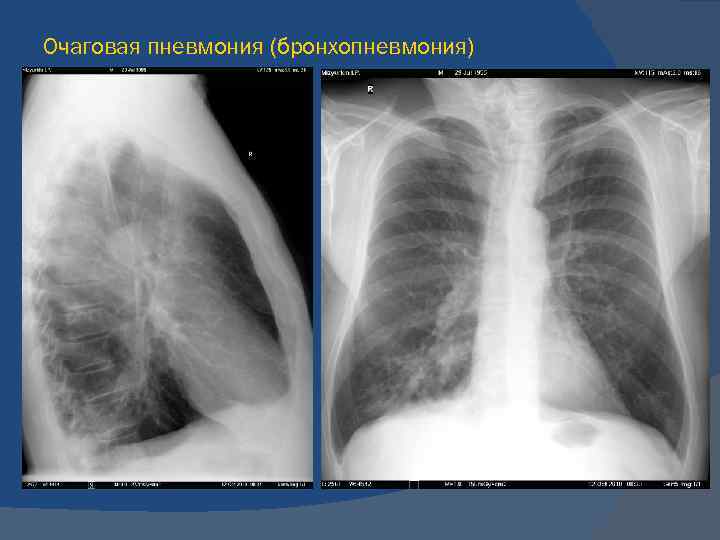

Ячеистая деформация легочного рисунка: медицинская визуализация